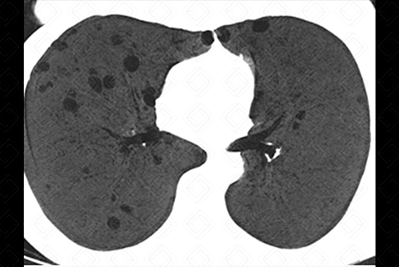

[cms-watermark] Descrição das figuras: Tomografia computadorizada com projeção em intensidade mínima - MnIP (mulher, 64 anos, portadora de síndrome de Sjögren). Múltiplos cistos, menores que 10 mm, de paredes finas e de distribuição bilateral.

• Tomografia computadorizada do tórax: A pneumonia intersticial linfocítica caracteriza-se pela presença de múltiplos cistos com distribuição randômica, isto é, aleatória, em adjacência a vasos sanguíneos. Nódulos pulmonares, usualmente, são achados encontrados em associação, auxiliando no diagnóstico diferencial com outras doenças císticas (figuras acima).